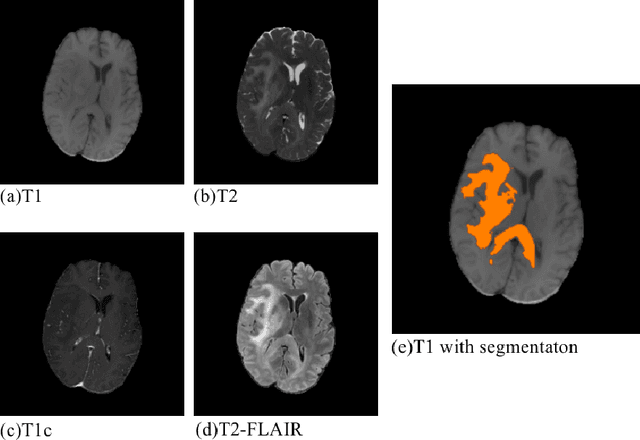

Abstract:Convolutional neural networks (CNNs) have recently achieved remarkable success in automatically identifying organs or lesions on 3D medical images. Meanwhile, vision transformer networks have exhibited exceptional performance in 2D image classification tasks. Compared with CNNs, transformer networks have an obvious advantage of extracting long-range features due to their self-attention algorithm. Therefore, in this paper we present a CNN-Transformer combined model called BiTr-Unet for brain tumor segmentation on multi-modal MRI scans. The proposed BiTr-Unet achieves good performance on the BraTS 2021 validation dataset with mean Dice score 0.9076, 0.8392 and 0.8231, and mean Hausdorff distance 4.5322, 13.4592 and 14.9963 for the whole tumor, tumor core, and enhancing tumor, respectively.